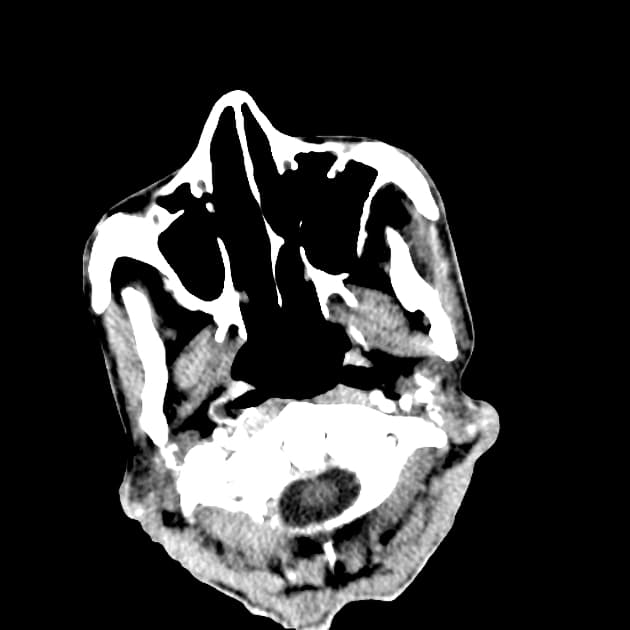

- Khối bắt thuốc dạng viền (ring-enhancing mass) ở thuỳ trán sau bên trái, kèm theo một lượng nhỏ phù vận mạch (vasogenic edema) xung quanh.

Lesion "hoàn hảo" bắt thuốc dạng viền, nhưng không phải là áp xe não (do không có hạn chế khuếch tán ở trung tâm trên hình ảnh khuếch tán – DWI và lượng phù tương đối ít). MAGIC DR là từ viết tắt gợi nhớ hữu ích cho hình ảnh này.

- "Lượng phù xung quanh tổn thương ít tương đối so với kích thước gợi ý u thứ phát hơn là u thần kinh đệm độ cao."